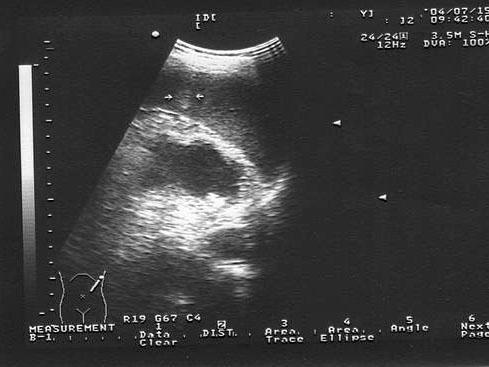

问题 男,25岁,例行体检时超声发现脾内占位。根据超声声像图诊断为?(?)

选项 A.血管瘤 B.淋巴管瘤 C.畸胎瘤 D.淋巴瘤 E.脾内钙化灶

答案 A